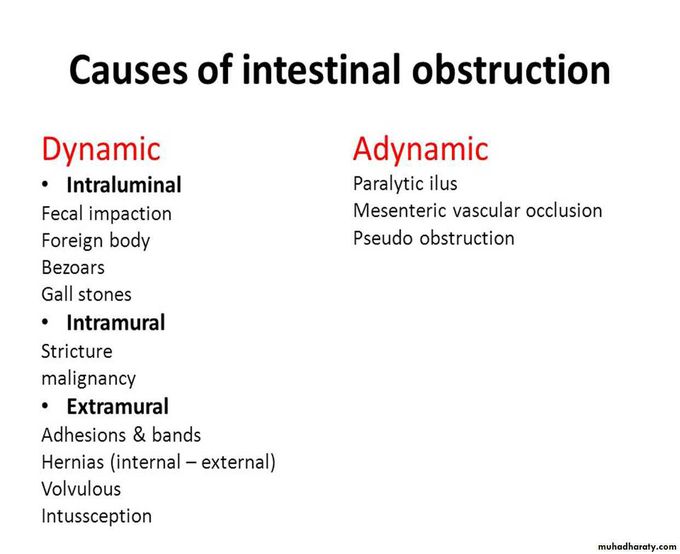

Intestinal Obstruction

Intestinal Obstruction

Intestinal Obstruction